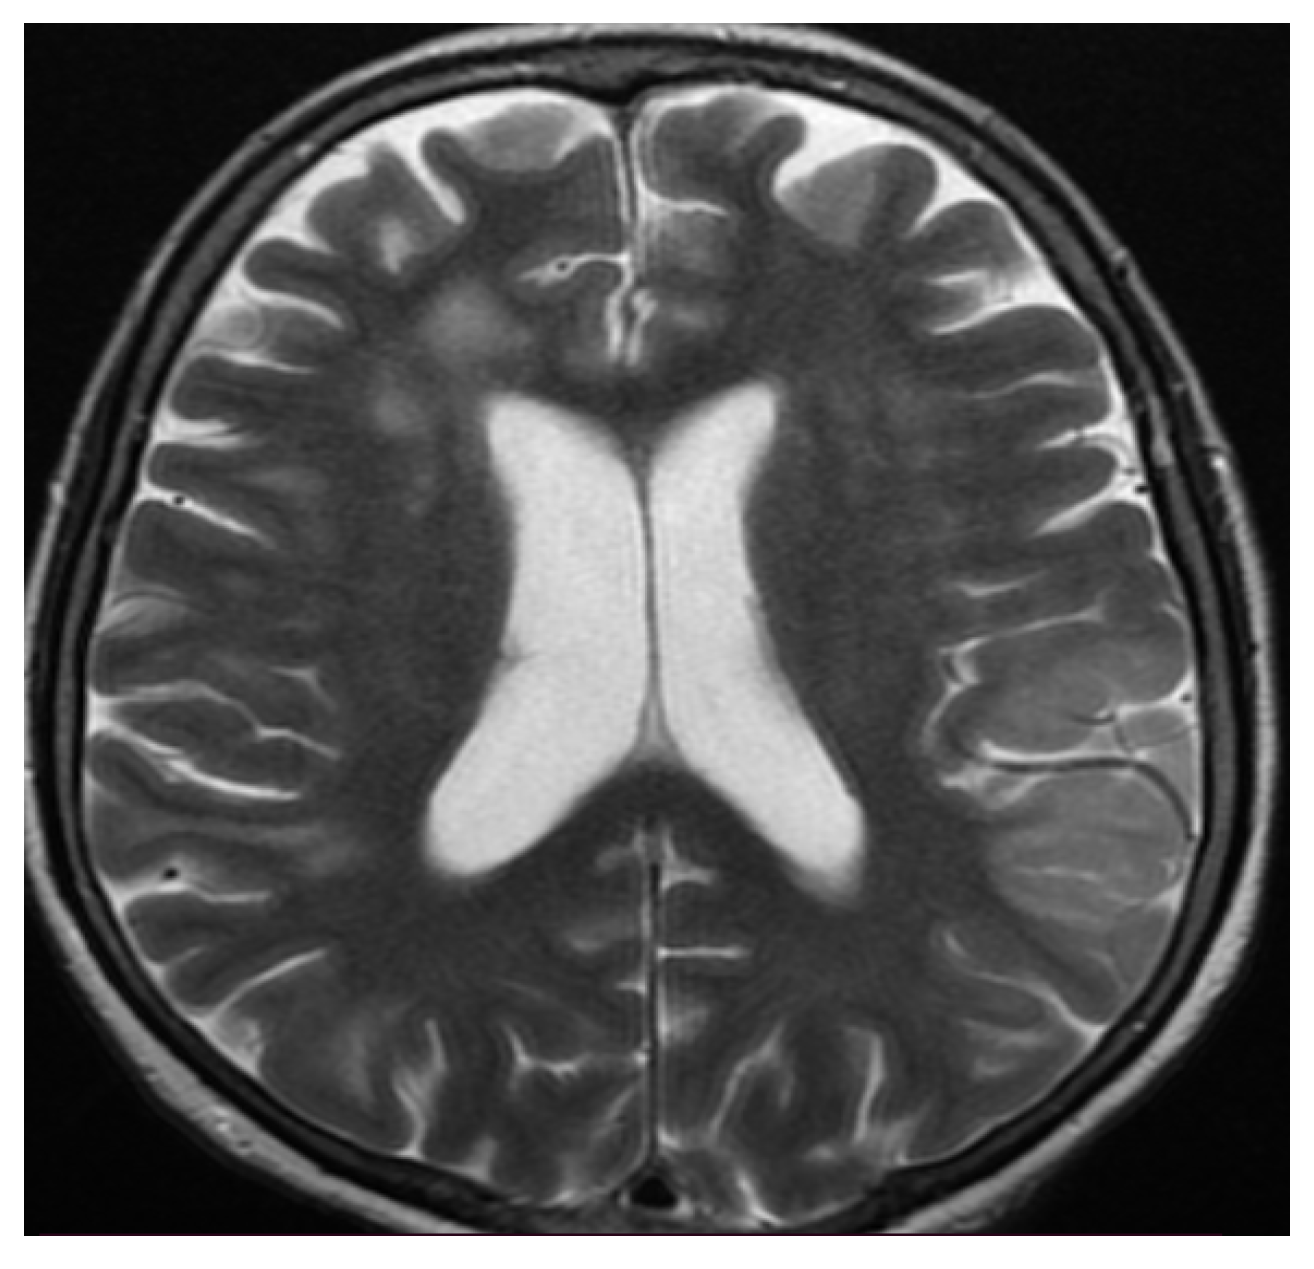

3.3. Neuroimaging